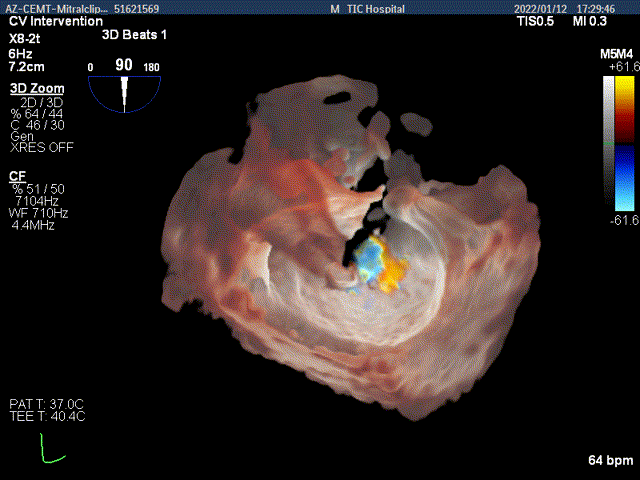

3Dview验证两个夹子的位置是否平行

3D-view验证两个夹子位置稳定,排列紧密

3D-Color-view验证微少量残余返流